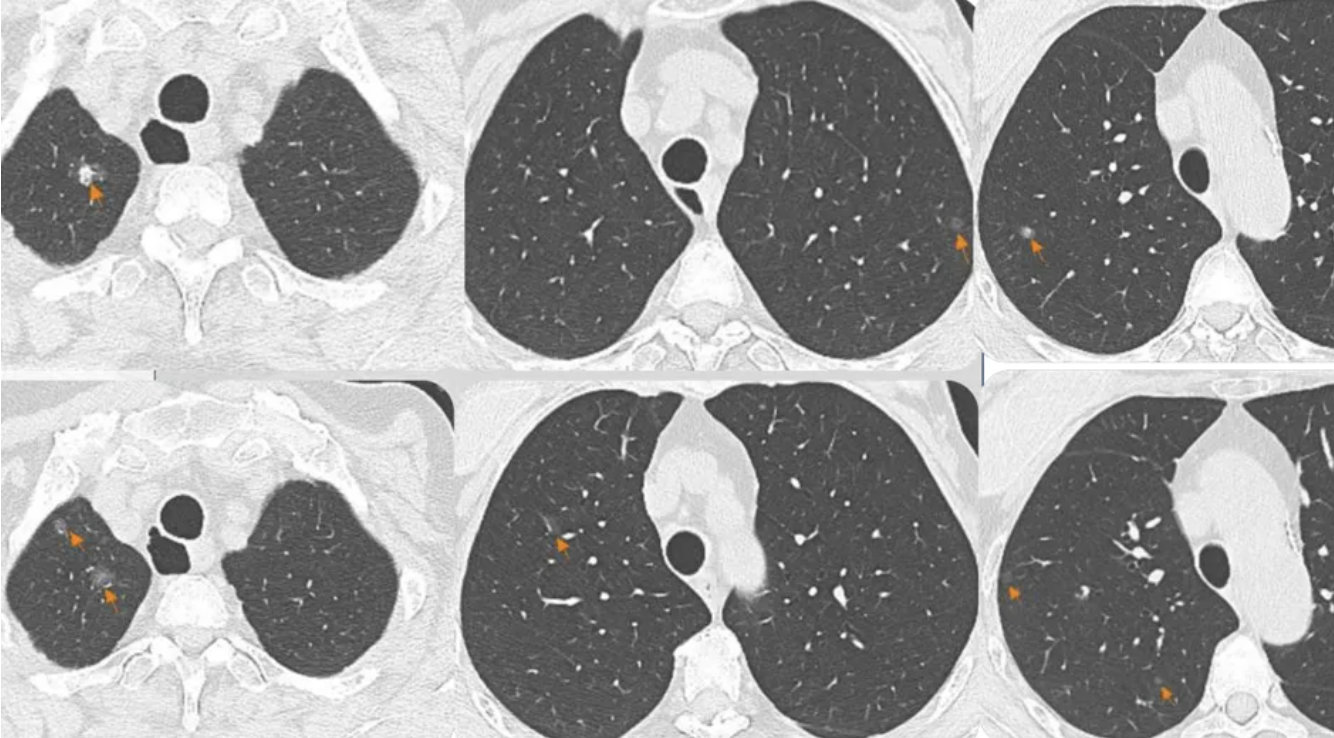

多原发肺癌(MPLC)的影像学特征,世界肺癌组织将其划分为四个类型。其中一类特征为双上肺多发的磨玻璃结节,因病灶进程与生长速度差异,可表现为纯磨玻璃结节、混合磨玻璃结节及实性结节共存。此多样性并存现象是其最具特征的影像学表现。

多发性肺磨玻璃密度高危结节,应考虑多原发肺癌的可能性。如前所述,MGGN肺癌的影像学特征在于呈现典型GGN征象,即界限清晰的纯磨玻璃影,可表现为纯磨玻璃结节、部分实性结节及实性结节并存,即多种磨玻璃结节病变并存。此类结节通常不伴有纤维条索样等“伴随影像征象”,且进展极为缓慢。纯GGO病理多为AAH、AIS和MIA;部分实性GGO病理多为MIA和IA。